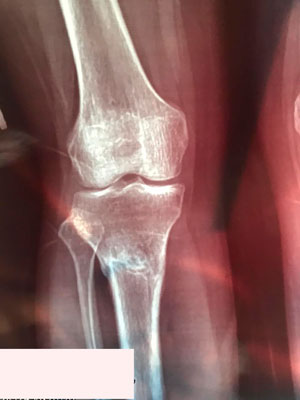

Исходник - 38 лет. Алматы.

Дата операции - 15.06.2019г.

Дата снятия аппаратов - 25.09.2019г.

Срок сращения - 100 дней.